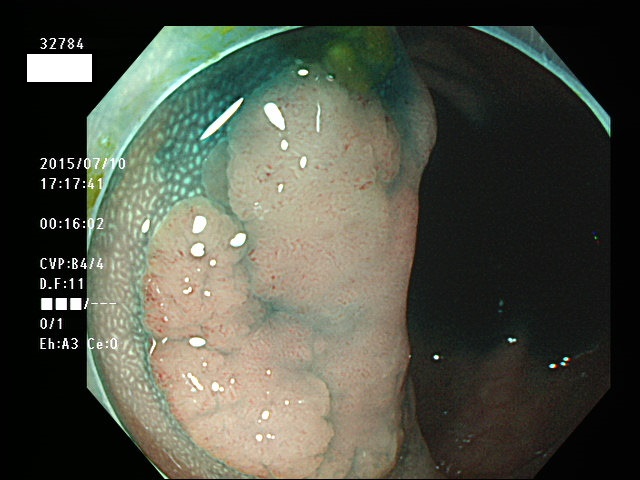

上記100名より抽出した平坦・陥凹型腺腫(=癌化の危険が高いが見落としやすい病変)の内視鏡写真

腺腫発見率 57% (カルテ番号32700〜32799の100名の方の検査結果で集計)

以下のカルテ番号の方に腺腫(Adenoma,Group3〜5)が見つかりました

32784 32787 32788 32790 32794 32795 32796 32798 32799・・・・・・の57名